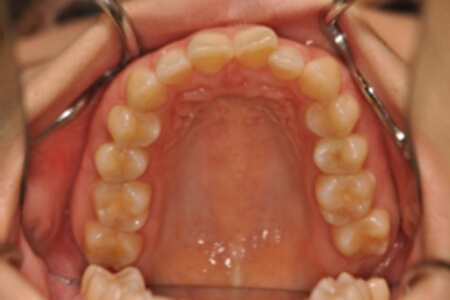

初診時

症例 症例 症例 症例

年齢

30歳 性 別 女性

治療期間 2年11か月 費 用 矯正施術料:1,000,000円

調整料:4,000円/月

治療内容の詳細 初診時30歳の女性で、全体的ながたつきを主訴として来院されました。

検査の結果、過蓋咬合を伴う、アングルⅡ級1類不正咬合と診断しました。

治療としては、非抜歯の上、セルフライゲーションブラケット装置(デーモンシステム)とマウスピース矯正装置(インビザライン)で歯の配列を行いました。

同時に顎間ゴムにて咬合関係の改善を行いました。

治療期間は2年11か月でした。